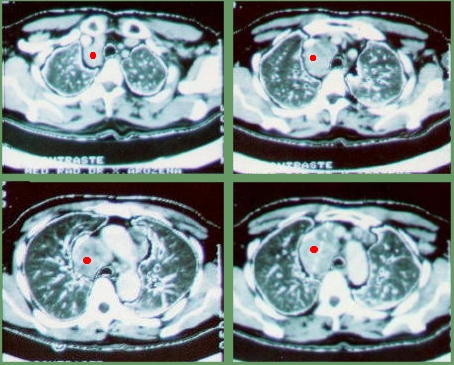

Tomografía Computarizada del Tórax

Evidencia una lesión de ocupación de espacio, ubicada en el mediastino anterosuperior, densa, homogénea de aspecto sólido de 8 cm. en su diámetro mayor, lobulada, adosada a la cava superior y se extiende transversalmente hasta la aorta ascendente con lesiones nodulares en la ventana aorto–pulmonar.